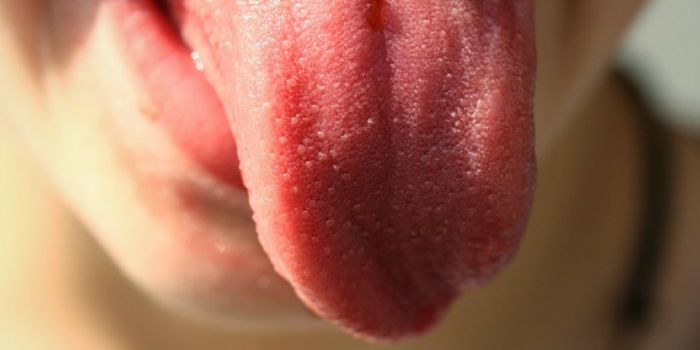

JUL 06, 2020MicrobiologyThe pandemic coronavirus has caused a wide range of different symptoms, and as time goes on, we may find that it can hav ...

JUL 05, 2020Cell & Molecular BiologyThe pandemic virus SARS-CoV-2 enters the body through the respiratory system to cause the illness COVID-19. But we know ...